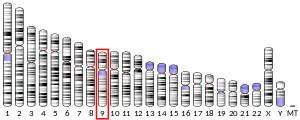

Location

The FOXE1 gene is located on the long (q) arm of chromosome 9 at position 22[7]